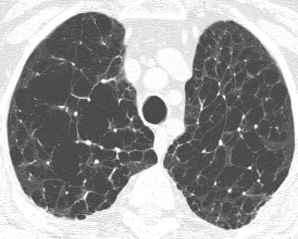

CT/HRCT

• More sensitive than chest radiography

• Emphysematous holes usually have no discernable wall

• Central artery may remain visible surrounded by destroyed lung

• Objectively measured by assuming that lung with a threshold HU < -960 is emphysematous lung

• Panlobular: involves entire lobule